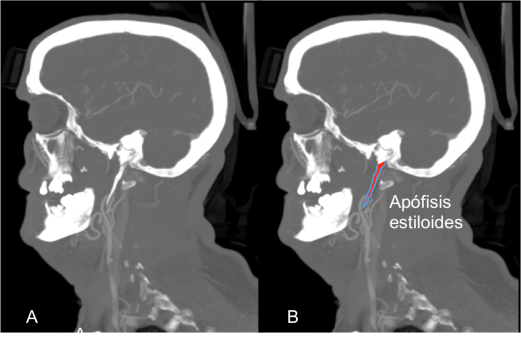

En la Figura 2. se puede observar la apófisis estiloides elongada en relación con el inicio de la disección de la arteria carótida interna izquierda.